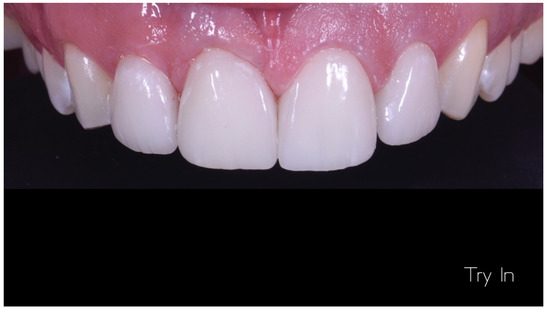

Case Report